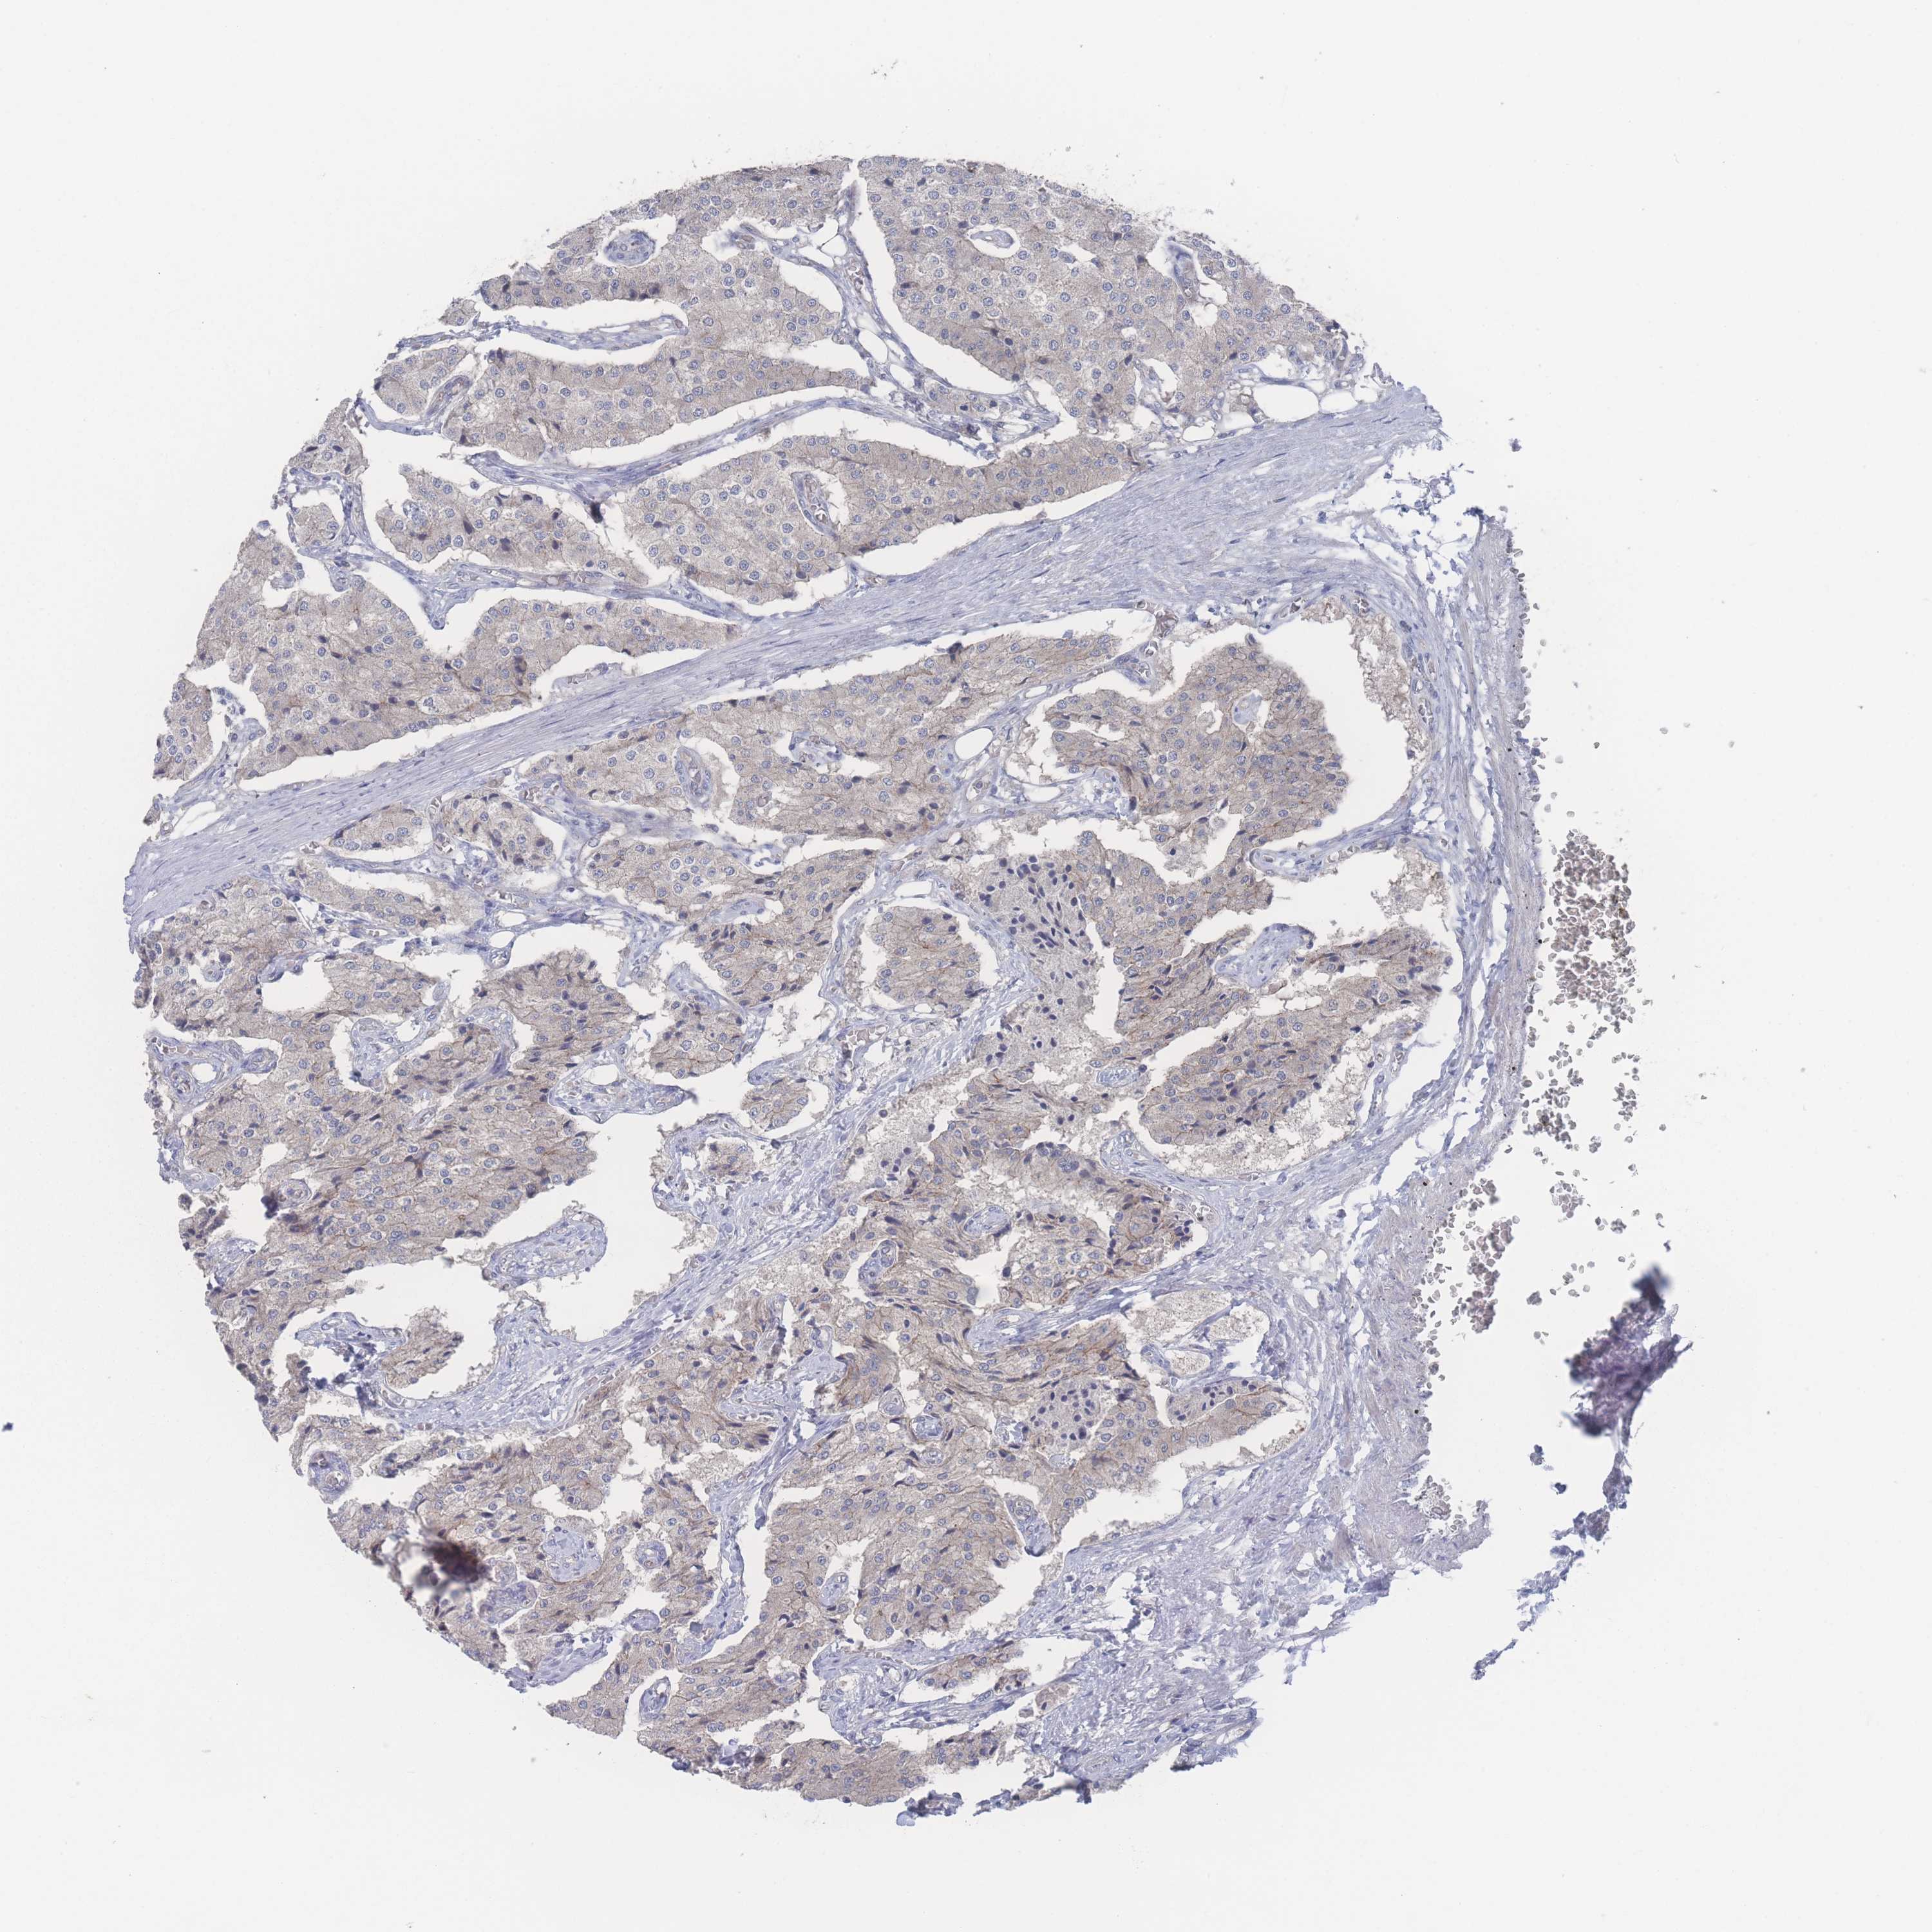

CARCINOID - Protein expressioni

A mouse-over function shows sample information and annotation data. Click on an image to view it in a full screen mode. Samples can be filtered based on level of antibody staining by selecting one or several of the following categories: high, medium, low and not detected. The assay and annotation is described here.

Antibody stainingi

Antibody staining in the annotated cell types in the current human tissue is reported as not detected, low, medium, or high, based on conventional immunohistochemistry profiling in selected tissues. This score is based on the combination of the staining intensity and fraction of stained cells.

Each image is clickable and will lead to virtual microscopy that enables deeper exploration of all samples and also displays staining intensity scores, fraction scores and subcellular localization as well as patient and tissue information for each sample.

Antibody HPA049189

Antibody HPA049447

Staining

High

Medium

Low

Not detected

Carcinoid, malignant, NOS

Carcinoma, NOS